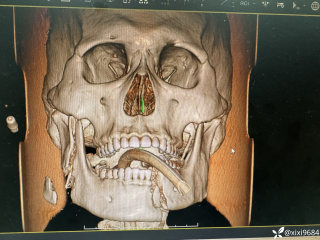

文/西地兰 特别声明:所有观点仅代表个人言论 特别声明:与当事双方均无利益相关 山东男孩,目前全网沸沸扬扬,看过一些观点,直言不讳地说,大多偏颇。要么一股脑地指责医方的全责,甚至有说千万别在县医院看病。要么又为医方无休止的遮羞,认为这样的手术在县医院做下来已经非常了不起。而我想到的是,以后面临类似的病例,我们怎么办?那么我们不如来一次专业的病案讨论。既然是事后讨论,难免有事后诸葛亮的感觉,但是假如下一次,同行们遭遇这样的病例,如何处置?这是医疗行业所面临的问题。希望我整理的这些思路和相关病例,对同行们有所帮助!就目前的资讯外界不足以判断是否需要急诊,如果需要急诊,那么只能根据术中所见进行处理,

目前知道的消息,第一,术前发现一个血肿,然后做增强CT发现一个占位,没说血肿与肿瘤的关系,术后病理没有描述肿瘤出现破裂出血,大概率就一个小血肿,我就不明白当地主任凭哪个指针去给这小孩开急诊刀的?哪个指南告诉他需要急诊开?第二,诊断不明确他想的不是进一步检查,一边观察一边进一步查,他反而选择腹腔镜探查,这个探查的指针在哪?第三,腹腔一个血肿,没有活动性出血,没有血压心率出现问题,为什么要开腹进去碰它?不能等血肿吸收再明确肿瘤性质吗?第四,1点进腹,3点病理结果出来,按这个时间还算顺利,应该还没出事,孩子还算平稳,病理是低度恶性,切了就治愈,他一年能开几台这手术,就敢继续做,拿孩子练手。第五,后面

2023年10月26日,来自山东菏泽市成武县的小烨和他家人的命运被彻底改变了。这个原本阳光、可爱的小男孩在一次意外被撞击后,在医院检查出了腹腔内存在肿瘤,并在手术中被切除了包括十二指肠、胰腺、大部分胃和小肠等多个器官。此后便无法再像正常人一样吃饭、喝水,活着要靠长期静脉注射营养液。一份2024年12月由第三方机构出具的司法鉴定意见书显示,当时给小烨做手术的成武县人民医院在该医疗行为中存在过错,与小烨的损害后果之间存在因果关系,建议医疗过错在损害后果中的原因力大小为同等原因。此外,另一份由成武县卫生健康局在2025年9月28日发出的书面答复中显示,成武县人民医院存在24小时内未完成病历;手术知情